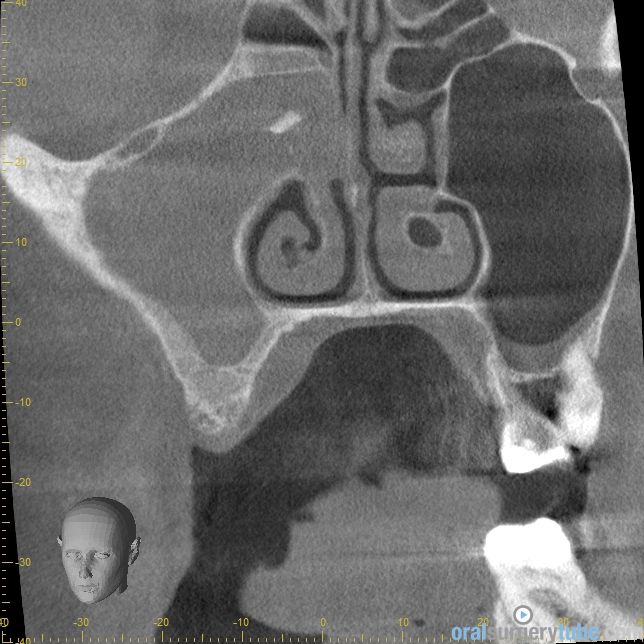

Cierre de comunicación orosinusal con tejido duro y blando